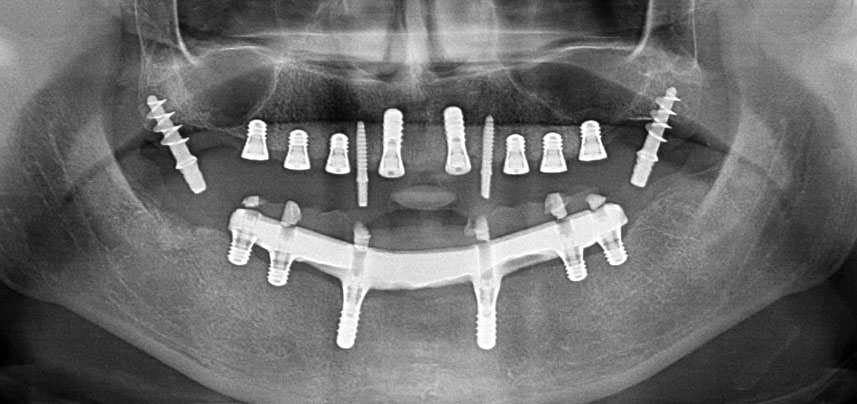

In pazienti edentuli, protesi fisse su impianti migliorano la masticazione e la qualità della vita. A causa del riassorbimento e dell'estesa pneumatizzazione dei seni, una paziente presentava solo una minima altezza dell'osso mascellare posteriore. Le sedi dell'impianto sono state preparate con un dispositivo piezoelettrico e un nuovo set di strumenti dedicati. Sono stati posizionati due impianti da 10 mm e sei da 4 mm per ancorare una protesi dentaria CAD/CAM fissa supportata da barra.

Tre anni dopo era il momento di una protesi dentaria mascellare dello stesso tipo. In base alla pianificazione con CBCT, il rialzo del seno mascellare è stato evitato con l'ausilio di impianti corti e una dima chirurgica è stata utilizzata per trasferire le posizioni pianificate alla cresta alveolare (Figg. 1 e 2).

A causa dell'osso relativamente duro (D2) in quest'area, le sedi dell'impianto di 10 mm nelle posizioni 11 e 21 sono state finalizzate con un trapano rotante da 4 mm di diametro, in combinazione con un contrangolo chirurgico W&H WS-75 L, il motore per impianto W&H Implantmed e il modulo opzionale Osstell ISQ di W&H. Al contrario, a causa dell'osso morbido, le sedi posteriori sono state preparate a un diametro finale di 3 mm utilizzando lo strumento Piezomed I3P. Gli impianti sono stati infine posti per via transgengivale sull'osteointegrato per tre mesi (Figg. 6-10). La protesi dentaria esistente è stata mantenuta su quattro impianti provvisori (Fig. 8).